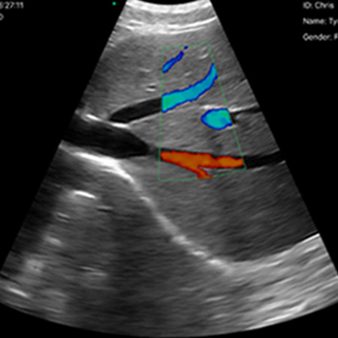

El escáner de ultrasonido portátil de doble sonda es una solución avanzada diseñada para ofrecer máxima versatilidad clínica en un solo dispositivo. Gracias a su tecnología integrada, combina tres modos de escaneo —convexo, lineal y phased array— permitiendo evaluar estructuras profundas, tejidos superficiales y realizar estudios cardíacos con alta precisión. Esta integración reduce significativamente los costos al reemplazar la necesidad de adquirir múltiples sondas por separado.

| Modo de escaneo | B, B/M, Color, PW |

B, B/M, Color, PW

Aplicaciones

Vascular